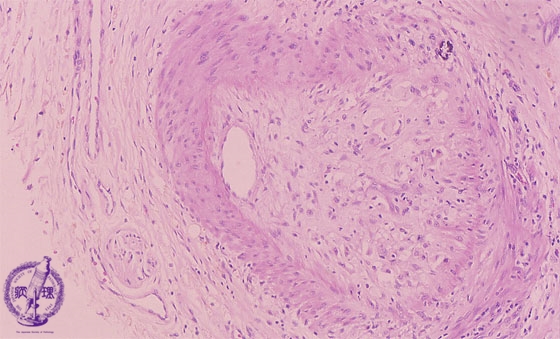

• 10.Liver

• (11)Transplantation rejection

Microscopic finding (HE stain, high power view): Foam cells infiltrate the portal hepatic artery intima and the latter undergoes fibrotic change with severe narrowing of the lumen.